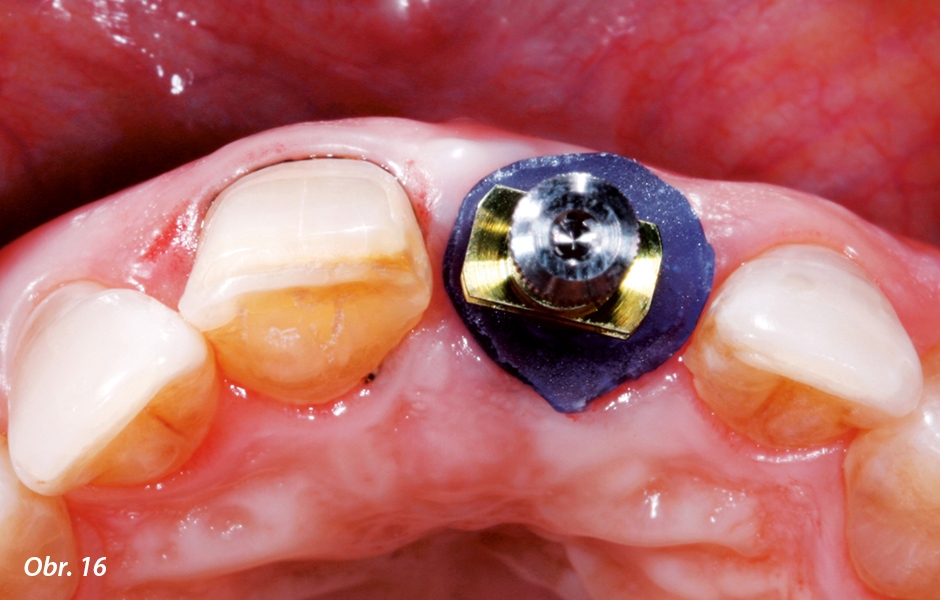

Po preparaci zubu 21 na keramickou fazetu byla provizorní korunka z implantátu opět sejmuta, bez jakékoli prodlevy byl na její místo zašroubován individualizovaný otiskovací člen (obr. 14) a pečlivě dotažen (obr. 15, 16). Individualizovaný otiskovací člen přejímá během otiskování podpůrnou funkci kvůli zabránění kolapsu a zachování vytvarovaného profilu periimplantárních měkkých tkání.5 Dostatečnou aproximální výškou je pak podpořena i oblast papil. Detailní otisknutí pozice implantátu a morfologie periimplantárních tkání včetně preparace na fazetu levého řezáku bylo provedeno polyéterovou otiskovací hmotou v laboratorně zhotovené individuální lžíci otevřenou technikou (obr. 17). Tímto postupem lze snadno a spolehlivě, beze ztráty informace, přenést situaci měkkých tkání na laboratorní pracovní model potřebný k výrobě definitivní protetické rekonstrukce.1, 6 Po sejmutí otisku byla provizorní korunka opět našroubována na implantát a na zubu 21 bylo k překrytí preparace na fazetu zhotoveno kompozitní provizorium z volné ruky (obr. 18).

Pečlivě přišroubovaný individualizovaný otiskovací člen přejímá během otiskování podpůrnou funkci pro periimplantární měkké tkáně. Při dostatečné aproximální výšce je dobře podepřena i oblast papil.

Pohled z incize ukazuje cirkulární oporu měkkých tkání během otiskování prostřednictvím individualizovaného otiskovacího členu